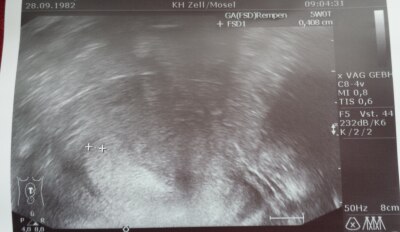

Montag darf ich endlich zum Arzt!!!!! War das letzte mal am 26.9 !!! Bin so aufgeregt weil ich nichts auf dem ultraschall gesehen habe obwohl die Frauenärztin was ausgemessen hat!!! Hoffentlich ist der krümel gewachsen!!! Hatte schon 2 fehlgeburten!!! Die tage ziehen sich wie kaugummi !!!

Bild zu hallo zusammen :-) - Forum für Mai - Mamis